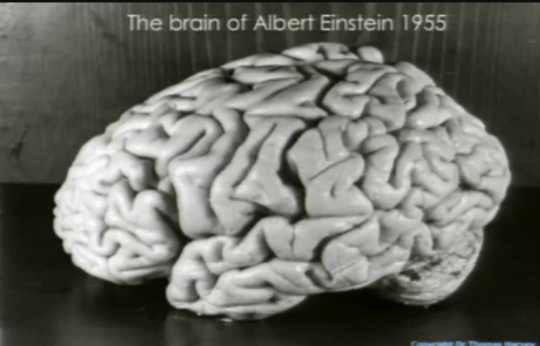

Τον πήρε μαζί του

Σύντομα ο Χάρβεϊ έχασε τη δουλειά του στο νοσοκομείο του Πρίνστον και πήγε τον εγκέφαλο στη Φιλαδέλφεια, όπου τον τεμάχισε σε 240 κομμάτια και τον συντήρησε σε σελοϊδίνη, μια σκληρή και ελαστική μορφή κυτταρίνης. Μοίρασε τα κομμάτια σε δύο βάζα και τα αποθήκευσε στο υπόγειό του.

-Στην αρχική έκθεση του 1985,

ο Χάρβεϊ και οι συνεργάτες του διαπίστωσαν ότι στην περιοχή Brodmann Area 39 -μια περιοχή όπου συναντώνται ο κροταφικός, ο βρεγματικός και ο ινιακός λοβός- η αναλογία νευρώνων προς γλοία του Αϊνστάιν ήταν σημαντικά μικρότερη από ό,τι ήταν στην ίδια περιοχή σε 11 άλλους εγκεφάλους ελέγχου.

Αλλά η ομάδα ελέγχου δεν ήταν τόσο ευρεία: Οι εγκέφαλοι προέρχονταν από άτομα ηλικίας 47 έως 80 ετών, ενώ ο Αϊνστάιν πέθανε σε ηλικία 76 ετών. Οι εγκέφαλοι ελέγχου ήταν επίσης φρέσκοι, ενώ ο

εγκέφαλος

του Αϊνστάιν είχε μαραζώσει σε υπόγεια και ψυγεία μπύρας για τρεις δεκαετίες. Ίσως το πιο προβληματικό είναι ότι η μέτρηση των κυττάρων είναι υποκειμενική υπόθεση και οι ερευνητές που έκαναν τις μετρήσεις των κυττάρων γνώριζαν ποιος ιστός ήταν του Αϊνστάιν και ποιος όχι.

-Το 1996, ο Χάρβεϊ

συνεργάστηκε με έναν επιστήμονα από την Αλαμπάμα και μέτρησε τους νευρώνες στην περιοχή Brodmann Area 9 του Αϊνστάιν – μέρος του μετωπιαίου φλοιού – καθώς και εκείνους πέντε ατόμων ελέγχου. Δεν υπήρχαν διαφορές στον αριθμό των νευρώνων ή στο μέγεθος των νευρώνων, διαπίστωσε η

μελέτη

, αλλά ο ιστός του Αϊνστάιν ήταν λεπτότερος από τους άλλους. Πιο πυκνά στοιβαγμένοι νευρώνες, υπέθεσαν οι συγγραφείς, σημαίνει ότι τα μηνύματα από κύτταρο σε κύτταρο διανύουν μικρότερες αποστάσεις, γεγονός που μπορεί να σημαίνει συνολικά ταχύτερη

επεξεργασία

. Αυτό είναι αρκετά τραβηγμένο. Όπως επισημαίνει ο Χάινς, το εύρημα βασίστηκε σε μόλις ένα τετραγωνικό χιλιοστό του εγκεφάλου του Αϊνστάιν.

-Το 1999, ο Χάρβεϊ

και οι Καναδοί συνεργάτες του έβαλαν τον εγκέφαλο του Αϊνστάιν σε ένα από τα πιο έγκυρα ιατρικά περιοδικά του κόσμου, το The Lancet. Βασιζόμενοι σε παλιές φωτογραφίες που είχαν ληφθεί από τον εγκέφαλο του Αϊνστάιν πριν αυτός κοπεί, οι ερευνητές ισχυρίστηκαν ότι ο Αϊνστάιν είχε ένα ανώμαλο μοτίβο αναδίπλωσης σε μέρος του βρεγματικού λοβού του, μια περιοχή που έχει συνδεθεί με τη μαθηματική ικανότητα. Ανέφεραν επίσης ότι οι βρεγματικοί λοβοί του ήταν κατά 15 τοις εκατό ευρύτεροι και πιο συμμετρικοί από εκείνους των εγκεφάλων της έρευνας. Για άλλη μια φορά, όμως, οι ερευνητές γνώριζαν ποιες φωτογραφίες έδειχναν τον εγκέφαλο του Αϊνστάιν.